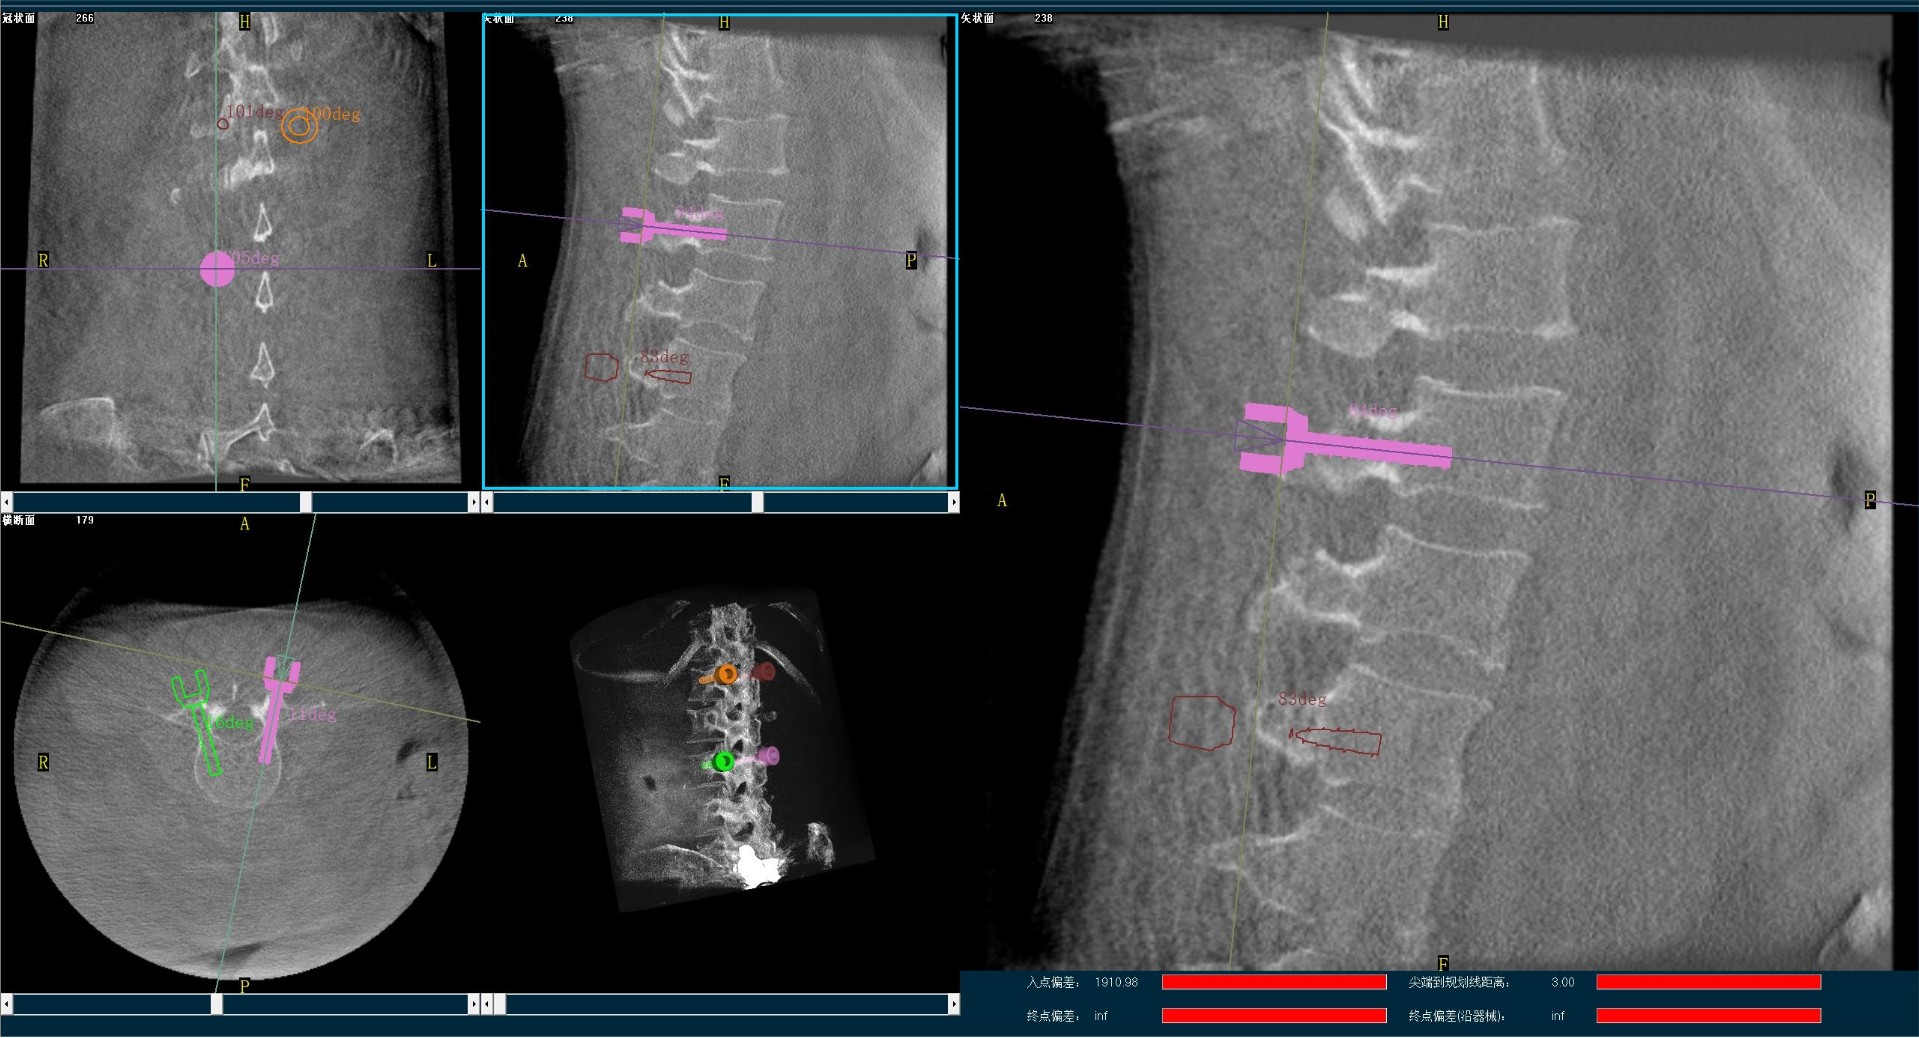

By using Perlove Medical’s flat panel 3D C-arm, frontal and lateral views of the lesion are taken to determine the exact location of the lumbar spine surgical segment. The sterilization is performed before the surgery. The navigation tracer is installed in the appropriate location, and the 3D images are captured and sent to the robotic navigation system. In the robotic navigation system, the corresponding vertebral body and screw specifications are selected according to the surgical needs, the surgical path is planned, and the surgeon in charge determines the insertion point and angle of pedicle screws.

*Preoperative Planning